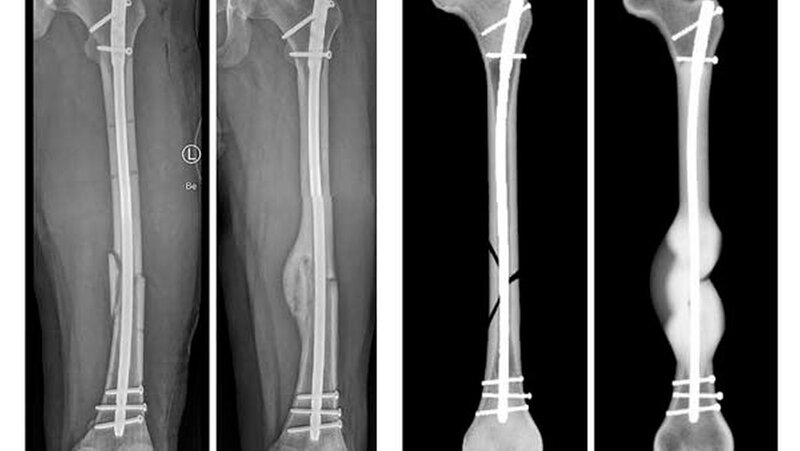

Für die Simulation wurden die klinischen Daten von 36 PatientInnen rückblickend analysiert. Diese hatten sich einen Schaftbruch des Oberschenkelknochens zugezogen, der durch die Implantation von Marknägeln versorgt worden war. Mithilfe von postoperativen Daten konnte die Computersimulation das Heilungsergebnis von 30 Fällen korrekt vorhersagen.

„Bisherige Studien zum Ulmer Frakturheilungsmodell basierten auf Daten aus Tierversuchen oder aus Versuchen unter Laborbedingungen. Die Kooperation mit dem UKU hat es uns nun ermöglicht, das Heilungsmodell erstmalig mit klinischen Daten zu testen. So konnten wir den Prototypen des Softwaretools weiterentwickeln”, erklärt Dr. Lucas Engelhardt von OSORA. „Das Heilungsmodell ist nicht nur in der Lage, Informationen zu erfolgreichen Heilungsverläufen zu generieren. Es wird ebenso zukünftig möglich sein, das Risiko für Komplikationen bis hin zu Pseudoarthrosen – also knöchernen Fehlheilungen – zu kalkulieren”, ergänzt Dr. Frank Niemeyer, ebenfalls von OSORA.

Nur in sechs Fällen – von denen zwei Knochenbrüche geheilt und vier nicht geheilt waren – war die Prognose der Computersimulation nicht korrekt. „Jeder Patient heilt anders, jede Fraktur hat ihre Besonderheiten. Wir können aus den Daten ableiten, warum die Simulation in diesen Fällen nicht den realen Frakturheilungsverlauf abbildet, um neben der Biomechanik weitere Einflüsse auf das Knochenwachstum im Modell mit zu berücksichtigen. Diese Informationen sind für die weitere Entwicklung unserer Softwareplattform von größter Bedeutung, um die Präzision der Vorhersage kontinuierlich zu erhöhen”, sagt Engelhardt.